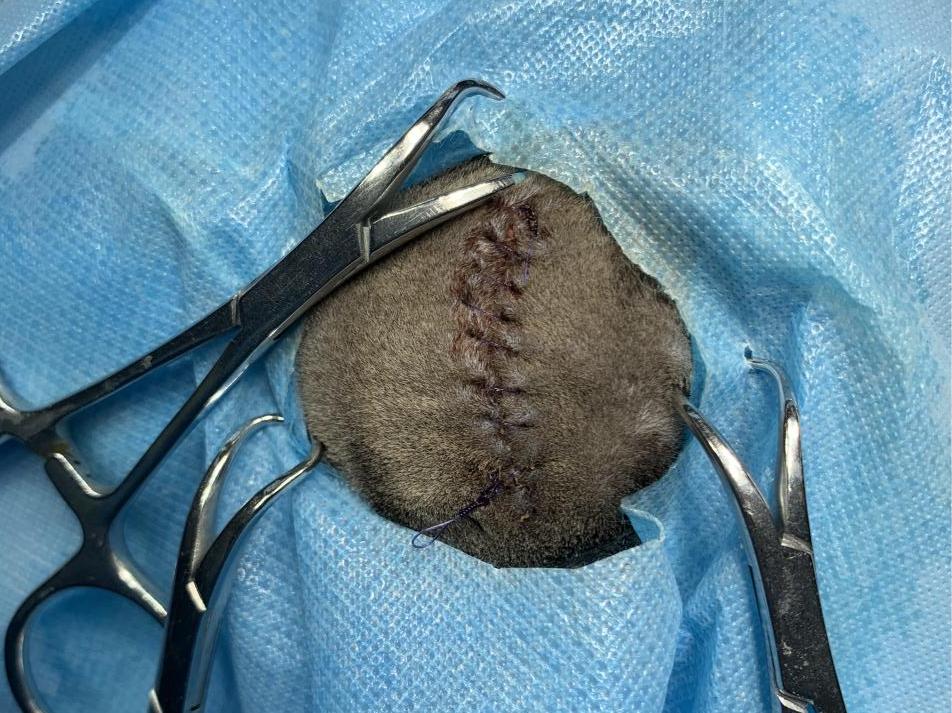

术后缝合伤口

手术取出组织送检病理排除肿瘤风险。